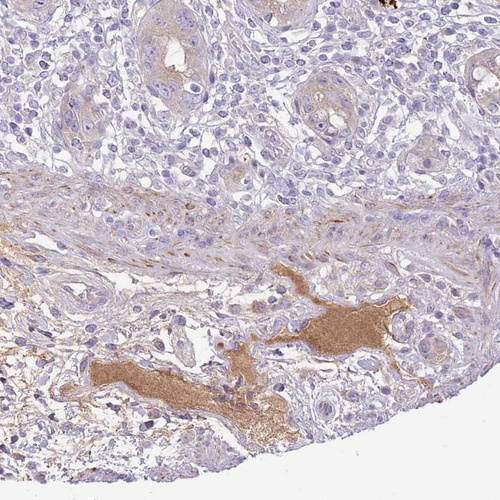

Immunohistochemical staining of human rectum shows strong positivity in plasma.